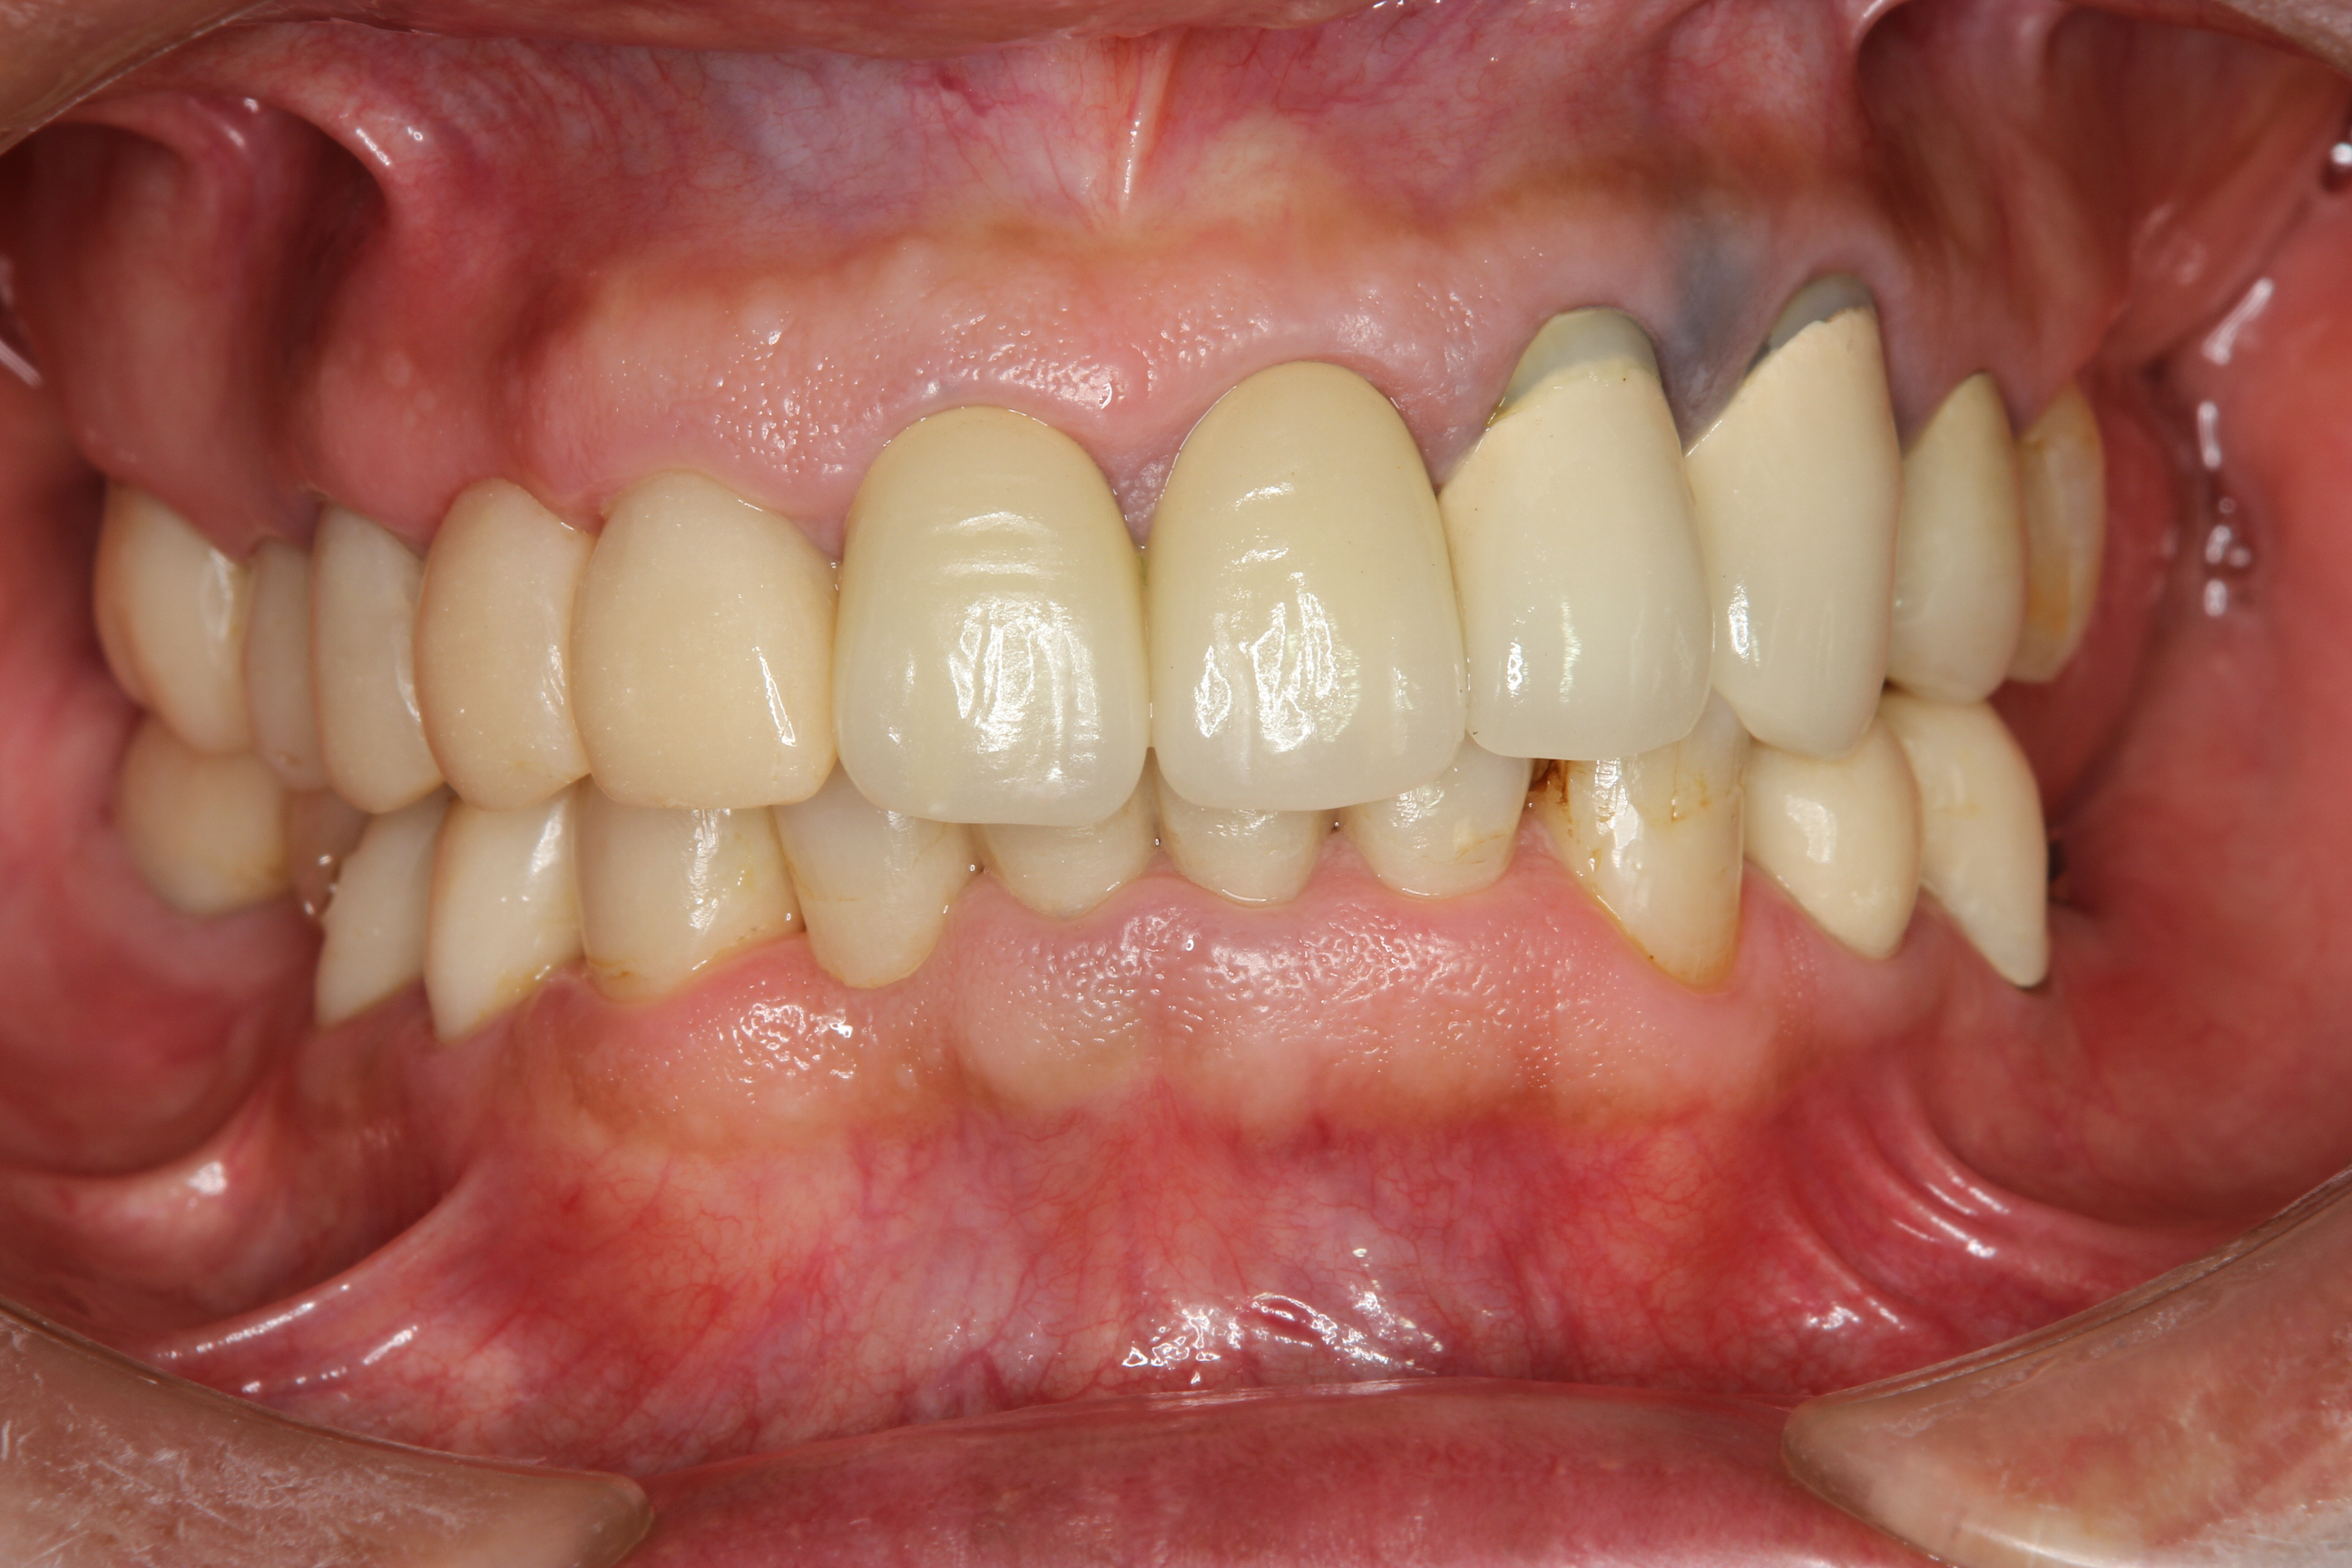

下の写真は、上顎と下顎の前歯部にメタルセラミックスクラウンを仮着(仮にセット)した時のものです。(下顎の臼歯部はまだ仮歯です。)

今後下顎の臼歯部にクラウンを装着し、予定していたすべての治療が終了です。

歯の欠損や歯冠形態の回復ができ、噛みあわせや見た目において大分改善しました。